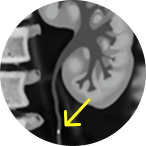

Jelmyto® (mitomycin) for pyelocalyceal solution is indicated for the treatment of adult patients with low-grade Upper Tract Urothelial Cancer (LG-UTUC).

This portrays real-world scenarios in which JELMYTO was used in a diverse range of tumor types. UroGen's Olympus trial studied patients with treatment-naïve or recurrent LG-UTUC with ≥1 measurable papillary tumor 5 to ≤15 mm located above the ureteropelvic junction (tumor debulking was permitted prior to study enrollment for tumors >15 mm).1 For additional inclusion and exclusion criteria, please see the Olympus trial study design.